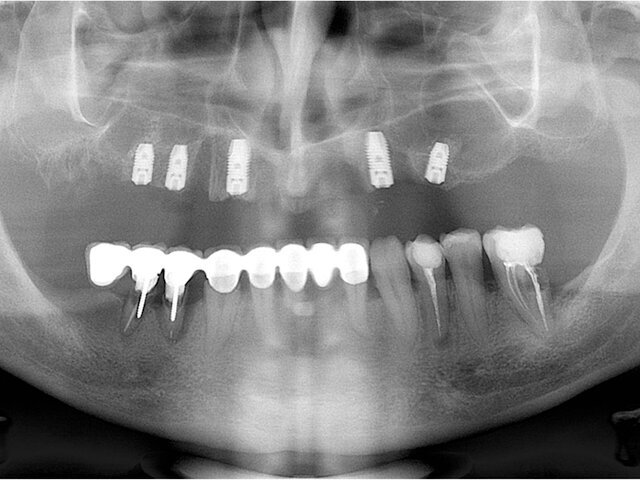

RTG finální nasazené práce

Konečná situace po 3 letech